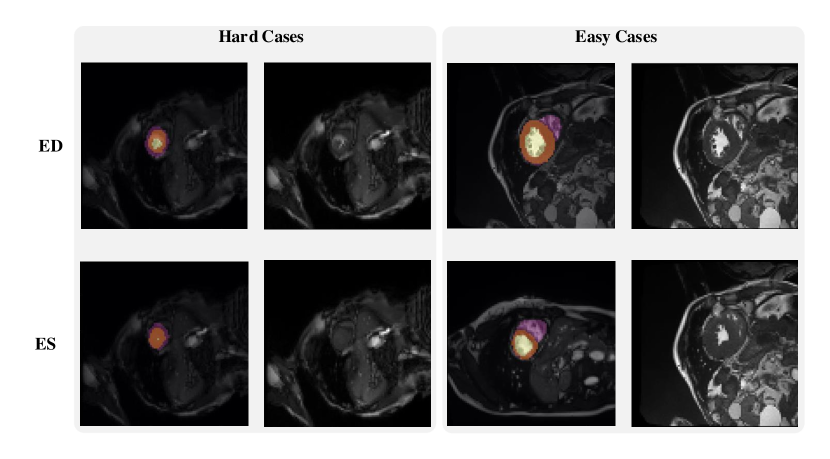

Refer to caption

Figure 2: Examples of hard and easy cases of CMR image (slice taken on short-axis). The first and second columns refer to hard cases and the third and forth columns refer to easy cases.

Figure 2 shows some hard and easy cases in both ED and ES phases of CMR image in the ACDC dataset. The hard cases usually have a low contrast, blur image, or extreme anatomical structure. While the easy cases have a high contrast, and less misleading structure with the similar features as LV, RV, and MYO have.